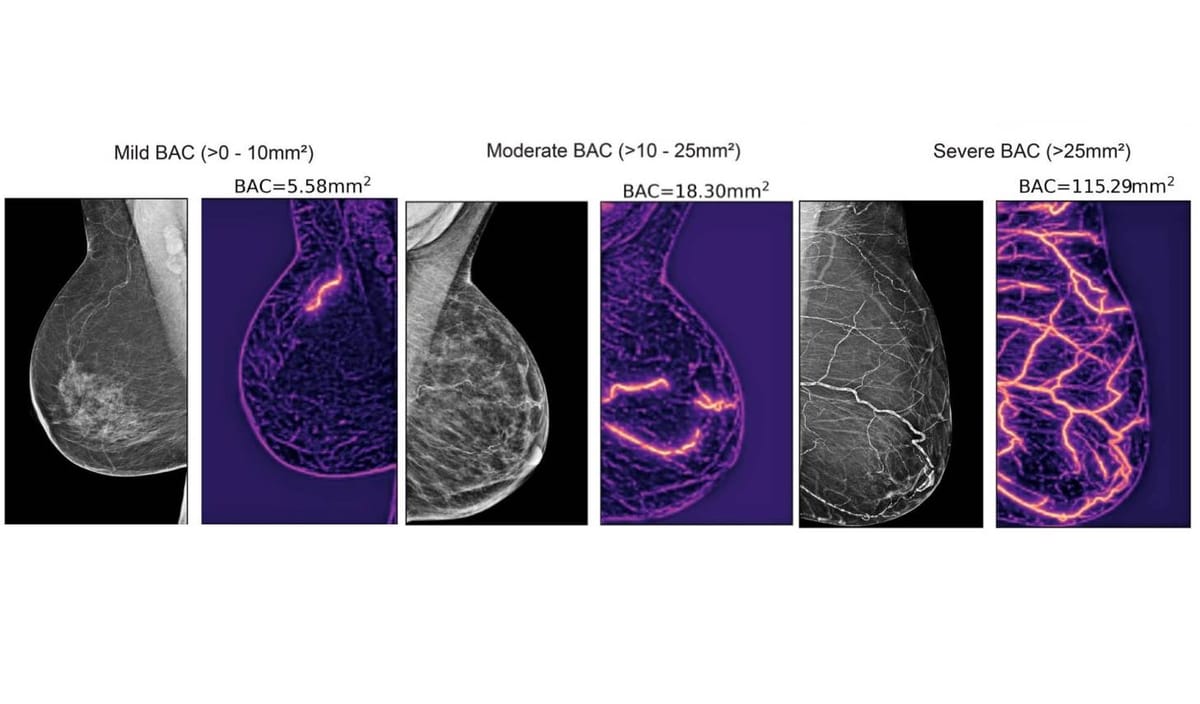

Traditional mammograms are designed to detect breast cancer. However, researchers have discovered that these scans also capture signs of breast arterial calcification (BAC), a buildup of calcium in the arteries that correlates with cardiovascular disease risk.

AI algorithms can analyze these patterns far more precisely than the human eye. By scanning mammogram images, machine learning systems quantify calcium deposits and other tissue characteristics associated with cardiovascular problems.

Researchers found that women with mild arterial calcification had about a 30% higher risk of cardiovascular disease, while moderate levels raised the risk by over 70%, and severe calcification increased it two to three times.